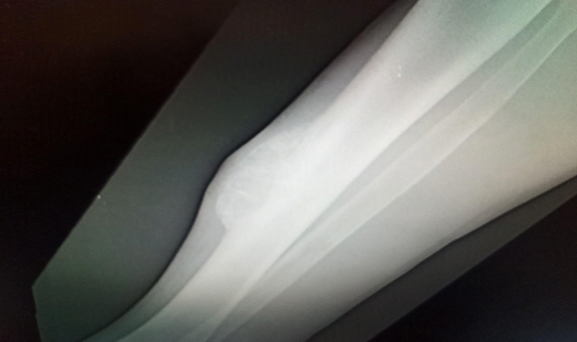

Valuation is completed: X-ray of the right leg: it highlighted the presence of a radiolucent lesion, with well-defined, clear borders, associated with discrete thinning of the adjacent bone cortex (subperiosteal resorption) and poor reactive bone tissue around it (Figure 3).

Figure 3 X-ray of the right leg showing a brown tumor.